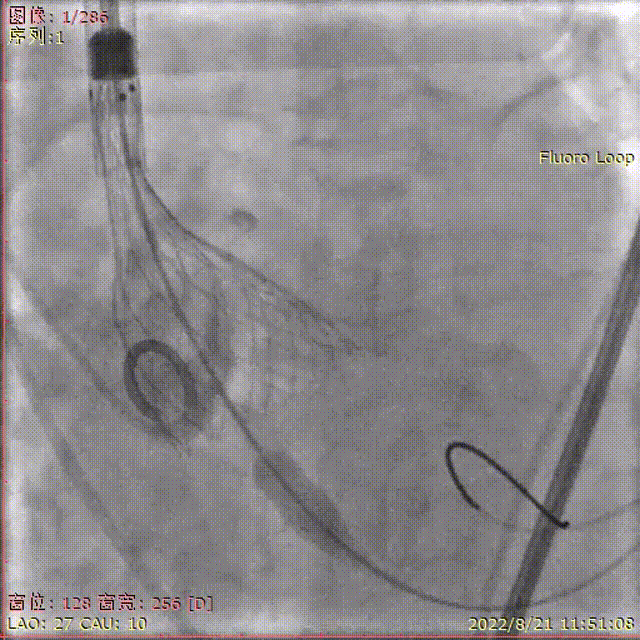

术中剪影

手术影像记录

18mm球囊预扩

输送器顺利过弓跨瓣

瓣膜初始定位

工作位多角度评估瓣膜形态,位置理想

缓慢稳定完全释放瓣膜

球囊后扩,改善瓣膜形态

最终造影,位置理想,无瓣周漏

外周造影检查